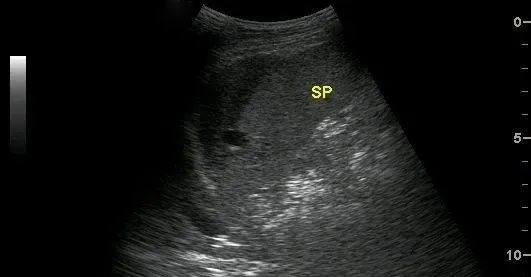

中央型脾破裂

是指脾臟實質內部的出血,在脾臟內形成血腫。

超聲表現為:脾臟實質內探及邊界清楚的非均質區,單發或多發,如伴有較大血腫時,非均質區內可探及不規則或類圓形無回聲區,透聲較差。